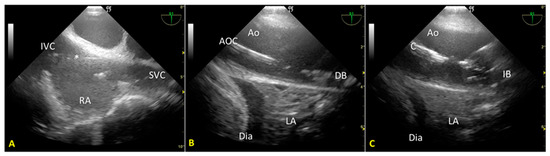

Cardiac arrest occurred rapidly with the cessation of life support. After checking the asystole on continuous ECG monitoring for twenty minutes (“no-touch period”), we certified the patient’s death. We performed post-mortem percutaneous femoral cannulation using the previously placed introducer wires. A 19 Fr cannula was placed in the right femoral vein (draining cannula) and a 17 Fr cannula in the right femoral artery (reinfusion cannula). Before starting the A-NRP, we inflated the AB according to the manufacturer’s instructions, which—considering the thoracic aorta diameter of 30 mm, as measured from a recent CT exam—was with 19 mL of saline (Figure 2A). We set extracorporeal blood flow to be greater than 2.4 L/min/m2, corresponding to half of the patient’s body surface area.

Nevertheless, abdominal aortic regional pressure remained consistently suboptimal (approximately 45 mmHg) [12]. A transesophageal color Doppler echocardiography scan to obtain a mid-esophageal descending aortic long-axis view demonstrated incomplete occlusion of the thoracic aorta (Figure 2B). Due to atheromatous plaques, the incomplete aortic occlusion required an additional 15 mL of saline. Real-time US-guided insufflation made filling the aortic balloon (AB) possible. AB is just enough to achieve total aortic occlusion but not so much as to risk balloon hyperinflation, which could cause aortic rupture, balloon rupture, and abdominal AB extension with celiac trunk occlusion (Figure 2C).

Figure 2. (A). Mid-esophageal descending aortic long-axis view scan: the endovascular occluder (RELIANT® catheter balloon, Tamworth, UK) is visible in the descending thoracic aorta. (B). Incomplete occlusion of the thoracic aorta during the initial phase of regional extracorporeal support for organ retrieval. Transesophageal color Doppler echocardiography documents the passage of blood around the aortic occluder. (C). Complete occlusion of the thoracic aorta after additional filling of the RELIANT® AB. Absence of blood flow in the thoracic aorta above the occluder. LA—lung atelectasis.